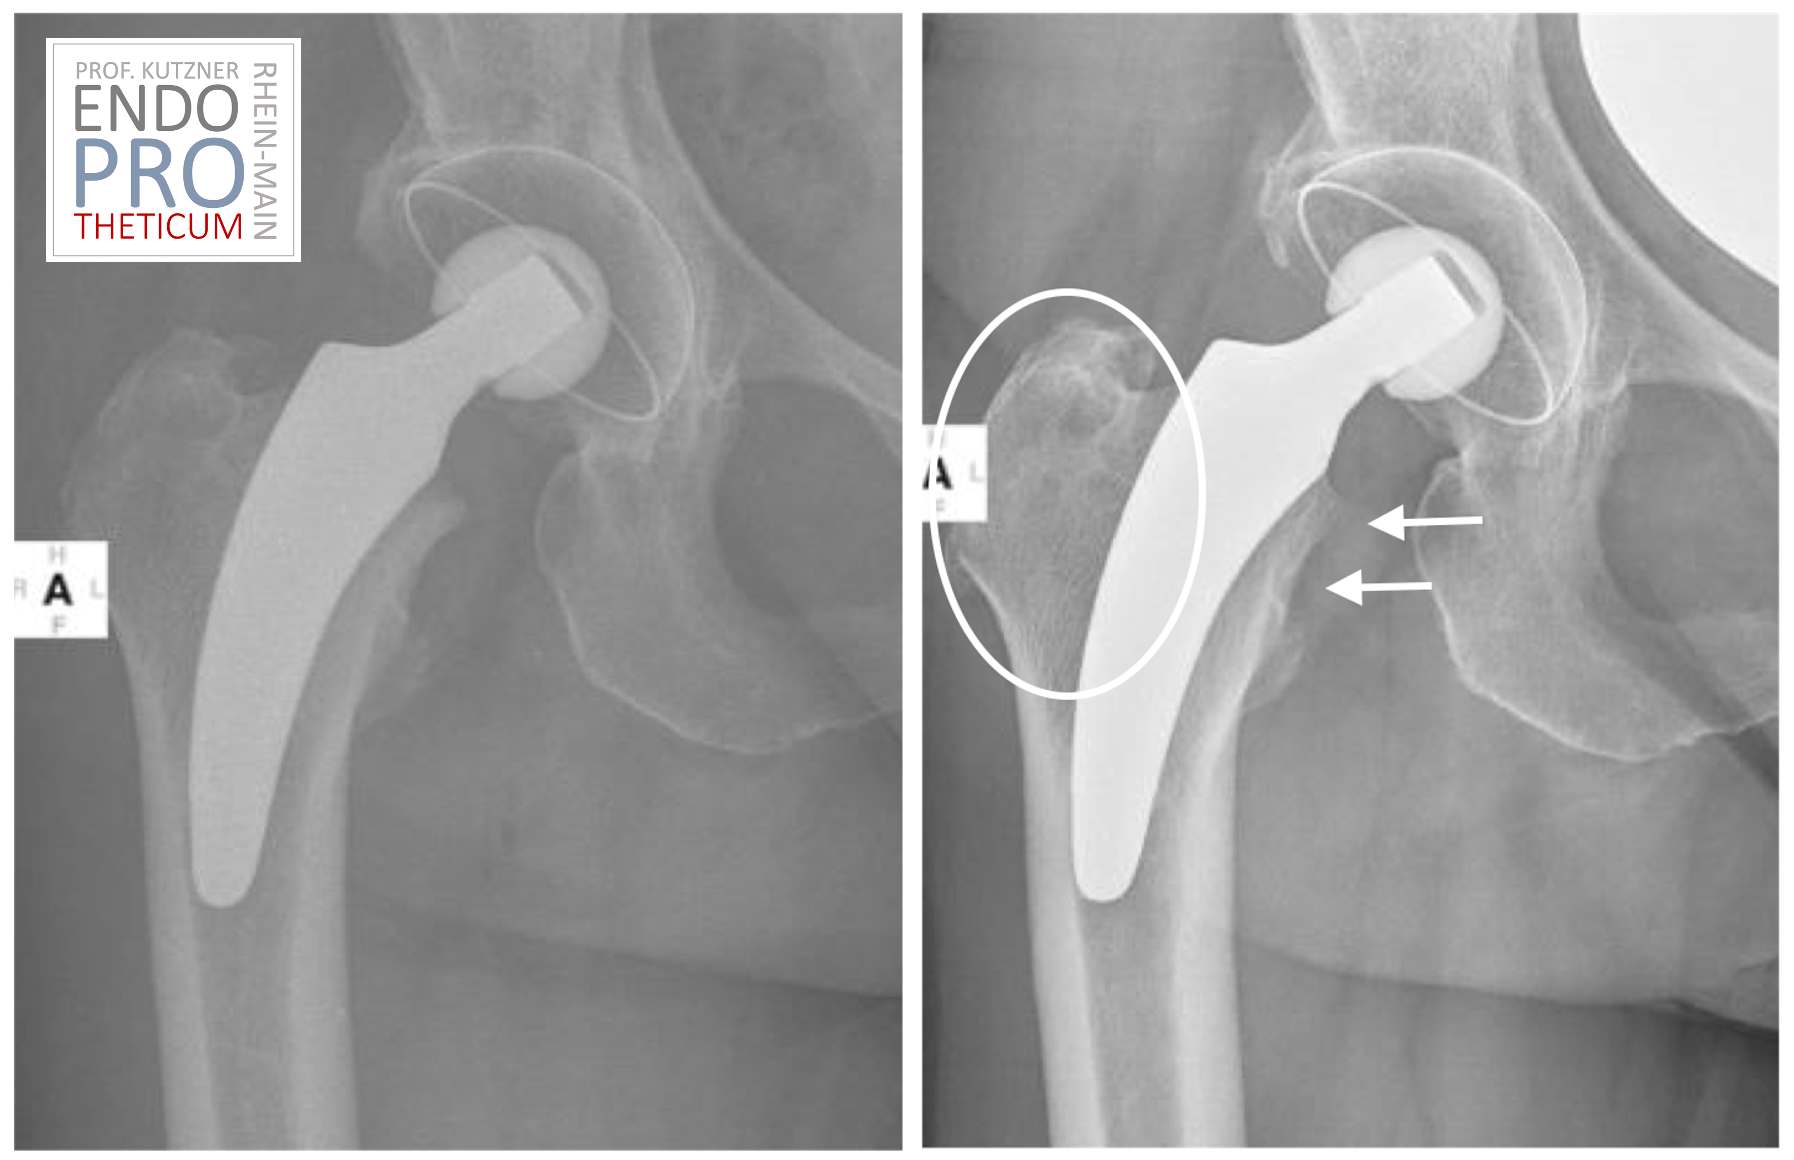

शॉर्ट-स्टेम कृत्रिम अंग ऐसे प्रत्यारोपण हैं जो विशेष रूप से हिप आर्थ्रोप्लास्टी के लिए विकसित किए गए थे और पारंपरिक प्रत्यारोपण की तुलना में शाफ्ट की लंबाई कम होती है। क्षतिग्रस्त या रोगग्रस्त ऊतक को बदलने और कूल्हे के जोड़ के कार्य को बहाल करने के लिए उन्हें फीमर में डाला जाता है। शॉर्ट-स्टेम कृत्रिम अंग कूल्हे के जोड़ की बेहतर स्थिरता और गतिशीलता प्रदान करते हैं, जिससे तेजी से रिकवरी हो सकती है और ऑपरेशन के बाद असुविधा कम हो सकती है।

छोटे तने वाले कृत्रिम अंग रोगियों के लिए कई संभावित लाभ प्रदान करते हैं। इनमें न्यूनतम इनवेसिव सर्जिकल तकनीक के कारण तेजी से रिकवरी, कूल्हे के जोड़ की बेहतर स्थिरता और सर्जरी के बाद अव्यवस्था या विस्थापन की कम संभावना शामिल है। इसके अतिरिक्त, उन्हें अक्सर सर्जरी के दौरान कम हड्डी हटाने की आवश्यकता होती है, जो फीमर की अखंडता को संरक्षित कर सकती है।

हालाँकि छोटे तने वाले कृत्रिम अंग कई संभावित लाभ प्रदान करते हैं, लेकिन वे हर रोगी के लिए उपयुक्त नहीं होते हैं। सभी चिकित्सा प्रक्रियाओं की तरह, शॉर्ट-स्टेम कृत्रिम अंग के उपयोग से जुड़े जोखिम और जटिलताएँ हैं, जिनमें संक्रमण, रक्त के थक्के और प्रत्यारोपण का ढीला होना शामिल है। अपने डॉक्टर के साथ इन जोखिमों पर चर्चा करना और यह निर्धारित करने के लिए संपूर्ण जोखिम-लाभ विश्लेषण करना महत्वपूर्ण है कि शॉर्ट-स्टेम कृत्रिम अंग आपके लिए सही विकल्प हैं या नहीं।